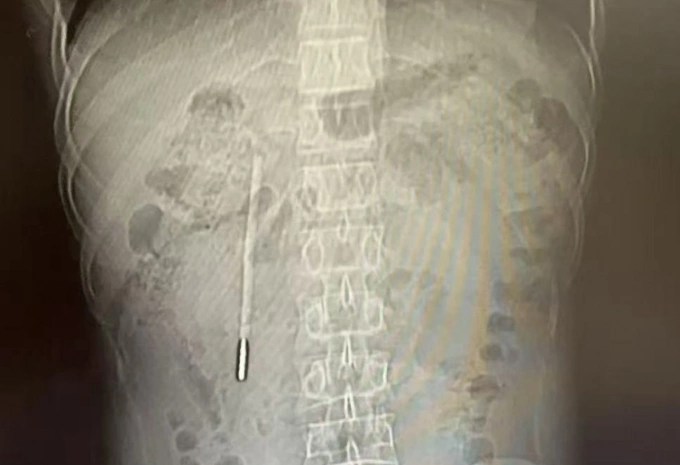

Phim chụp cho thấy một chiếc nhiệt kế thủy ngân trong bụng bệnh nhân. Ảnh: Wenzhou Metropolitan Daily